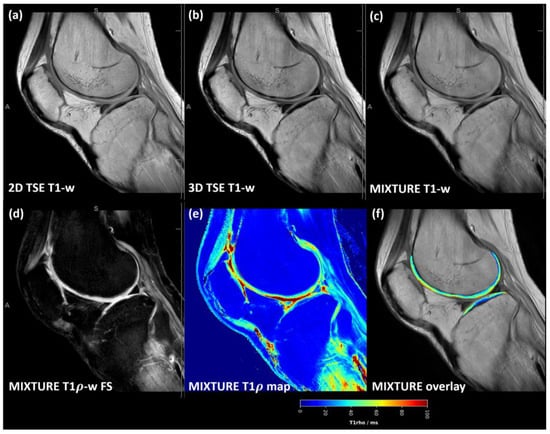

3.3. MIXTURE T1-Weighted Images Showed Slightly Increased Blurring

Across the acquired sequences, contrast, signal, and microstructural details appeared largely similar, although slightly more blurring was observed for the MIXTURE T1-w images (Figure 4 and Figure S2). Consequently, Weber contrast, CNR, and CV values were not significantly different (Figure 3d–f).

Figure 4. T1-weighted images acquired using the MIXTURE and corresponding reference sequences. The 2D TSE image (a), the 3D TSE image (b), and the MIXTURE image (c) are shown alongside the MIXTURE T1ρ-weighted fat-saturated image with 50 ms spin lock time (d), the MIXTURE T1ρ map (e), and the segmented cartilage tissue overlay (f). In this example, the segmented area of femoral and tibial cartilage exhibited mean T1ρ relaxation times of 45 ± 14 ms and 38 ± 14 ms, respectively (mean ± standard deviation). As for the MIXTURE T2 maps (Figure 2 and Figure S1), the MIXTURE T1ρ map did not yield meaningful values in areas of fatty tissue. Same slice and joint as in Figure 2. Abbreviations: -w—weighted, FS—fat saturated. MIXTURE—Multi-Interleaved X-prepared Turbo Spin-Echo with IntUitive Relaxometry. Supplementary Figure S2 provides a close-up of the femoral and tibial cartilage of the weight-bearing region.